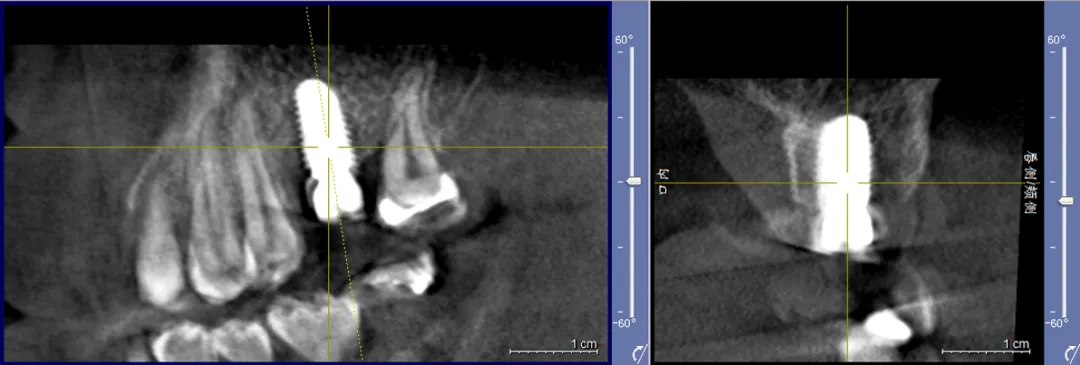

病例分享:患者男,诊断左上六慢性根尖炎劈裂;处置:基础治疗+即刻种植(种植前中后进行光动力疗法照射1min(2次)